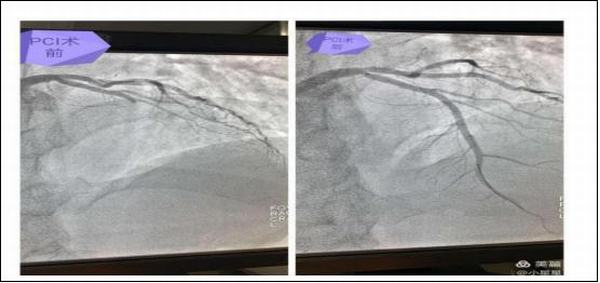

15分钟后,患者王先生在家属的陪同下来到了延安大学咸阳医院心血管病院11楼心六科,在吴医生问诊及查体时患者胸痛再次发作,并于4点20分突然出现四肢抽搐、呼之不应,触摸颈动脉搏动消失,呼吸呈叹息样,立即予以心肺复苏术,心电监测提示心室停搏,与此同时我科杨登魁责任总医师、我院心一科王银涛医师、心二科代雪茹医师、心三科王岩医师、留夜护士陈娜、心七科徐云鹏医师、留夜护士高谦闻讯赶来,并立即投入紧张的抢救过程中,经予持续胸外按压、多次电除颤等治疗后患者于4点40分意识逐渐恢复,心电监测示加速性室性自主心律,抢救成功,而早己就位的导管室同仁也做好了准备工作,并于6点40分成功开通了患者闭塞血管,术后患者生命体征平稳。

急性心肌梗死是因冠状动脉出现急性阻塞,心脏肌肉因缺乏血液供应出现坏死,使得心脏功能受损的一种危及生命的急性病症,时间就是心肌,时间就是生命,及时就诊是挽救生命的重要手段!正是因为我院有这样团结协作的团队,一次次挽救患者生命的经历,让心内科的每一名医护人员时刻牢记使命,不忘初心,重视细节安全,人性化服务,在追求卓越、精益求精的守卫患者健康的道路上一路领先,在患者心中树立良好口碑。